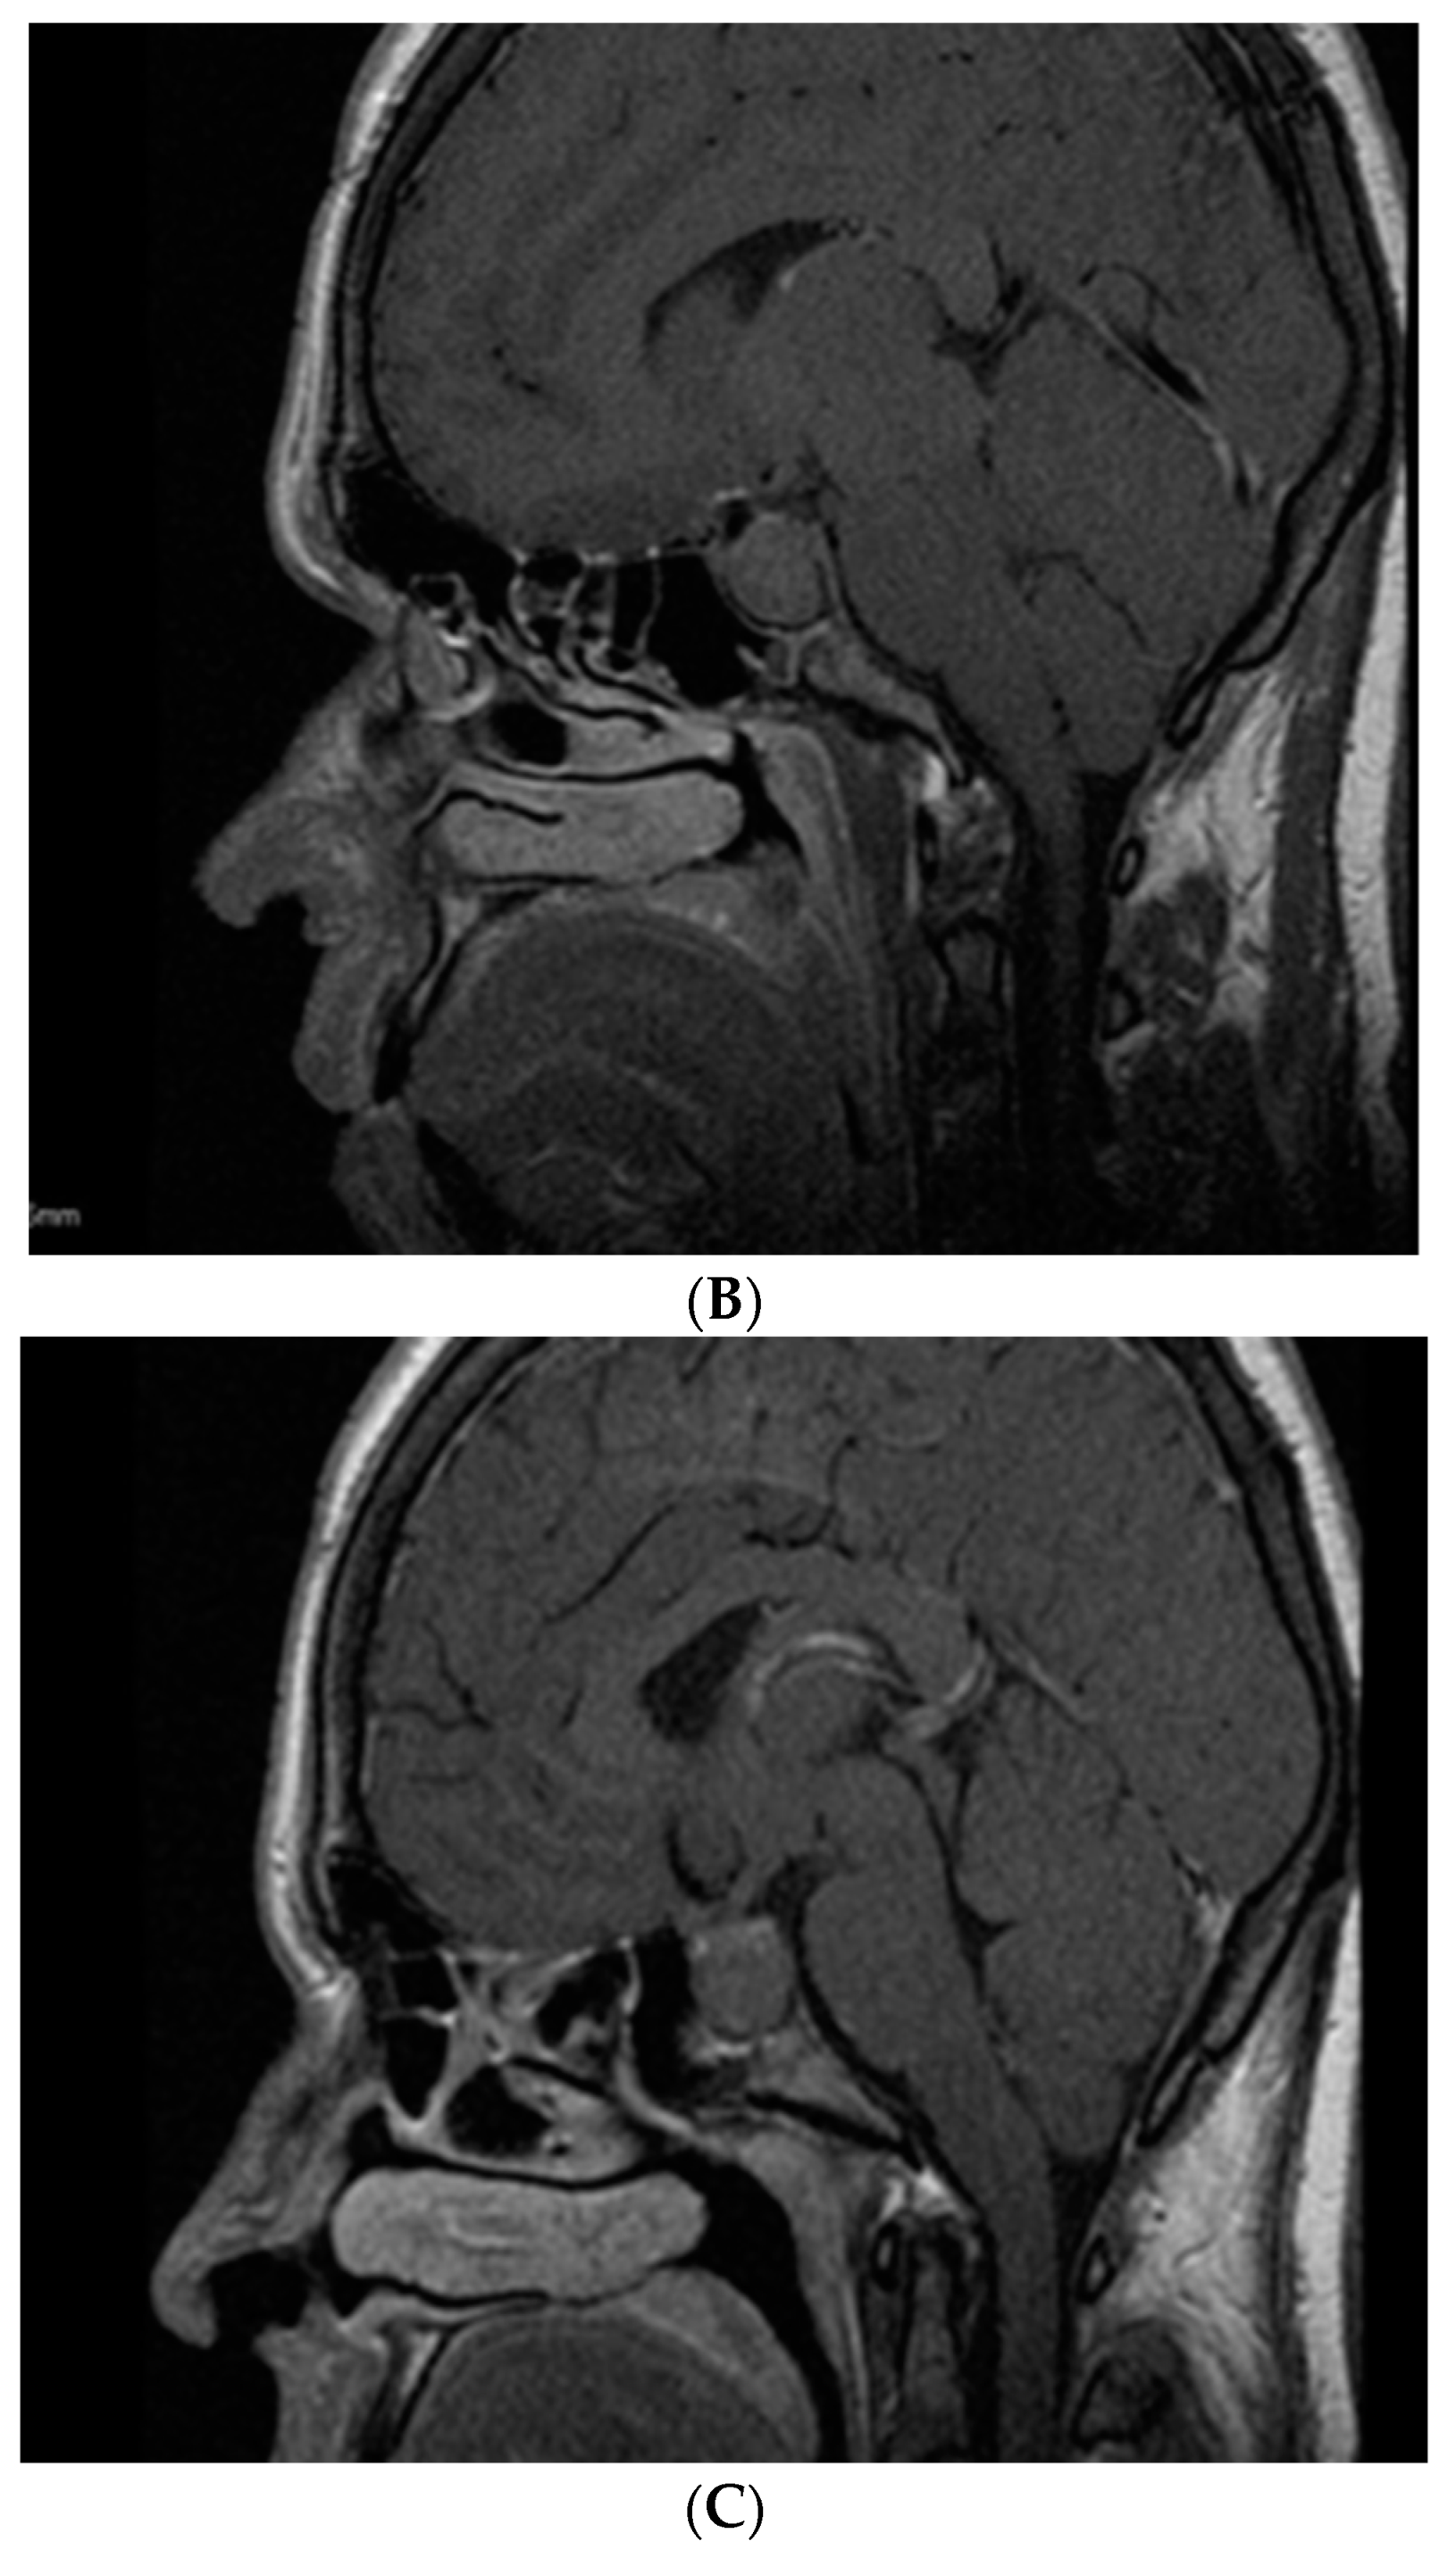

- Dicuonzo, F.; Purciariello, S.; De Marco, A.; Guastamacchia, E.; Triggiani, V. Inoperable Giant Growth Hormone-secreting Pituitary Adenoma: Radiological Aspects, Clinical Management and Pregnancy Outcome. Endocr. Metab. Immune Disord. Drug Targets 2019, 19, 214–220. [Google Scholar] [CrossRef]